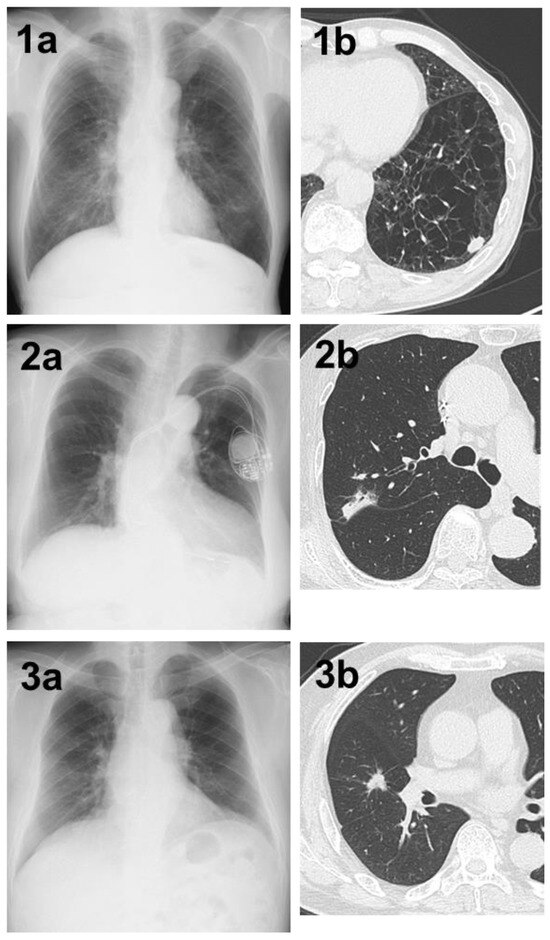

The main reasons why lung tumors could not be detected by the AI in 84 cases are listed in Table 2. Thirty-five cases had lesions overlapping with anatomical structures, such as the mediastinum, heart, and clavicle, or lesions below the diaphragm. Eight of these 35 cases were detectable by physicians (Figure 1). Conversely, there was one case in which it was difficult for physicians to detect the shadow overlapping the anatomical structures, but it was detected by AI (Figure 2). Eighteen cases were AIS, thirteen were lepidic adenocarcinoma (invasive size: 0.05–2.0 cm), and six were small nodules less than 0.7 cm in diameter. The other six cases were difficult to visualize on chest radiographs. Of these six cases, three cases had ground-glass components as the main component on CT, and one case had nodule and pulmonary vessels visible in succession. Many of these lesions were difficult to visualize due to the imaging conditions. Six patients did not fit these conditions; their lesions could be determined by physician interpretation, and their non-detection was judged to be an oversight by the AI (Figure 3).

Figure 2. (a) Although it was difficult for physicians to determine the abnormal shadow, AI was able to highlight a shadow overlapping the clavicle in the right upper lung field. (b) Chest CT showing a nodule with a total and solid size of 1.6 cm in the right S1 region. The histopathological diagnosis was adenocarcinoma (papillary adenocarcinoma), total tumor and invasive size of 1.8 cm, pT1bN0M0 (stage IA2).

Figure 3. (1a) A shadow in the left lower lung field that was not determined by AI. (1b) Chest CT showing a nodule with a total and solid size of 1.5 cm in the left S⁹ region on the basis of strong emphysematous changes in the lung. The histopathological diagnosis was squamous cell carcinoma, total tumor and invasive size of 1.5 cm, pT1bN0M0 (stage IA2). (2a) A shadow in the right upper lung field that could not be determined by AI. (2b) Chest CT showing a nodule with a pleural indentation, total size of 2.8 cm, solid size of 2.3 cm, in the right S2 region. The histopathological diagnosis was adenocarcinoma (papillary adenocarcinoma), total tumor and invasive size of 3.4 cm, pT2aN0M0 (stage IB). (3a) A shadow in the right middle lung field that could not be determined by AI. (3b) Chest CT showing a nodule with a total and solid size of 1.5 cm in the right S⁴ region. The histopathological diagnosis was adenocarcinoma (acinar adenocarcinoma), total tumor size of 1.5 cm, invasive size of 1.4 cm, pT1aN0M0 (stage IA2).